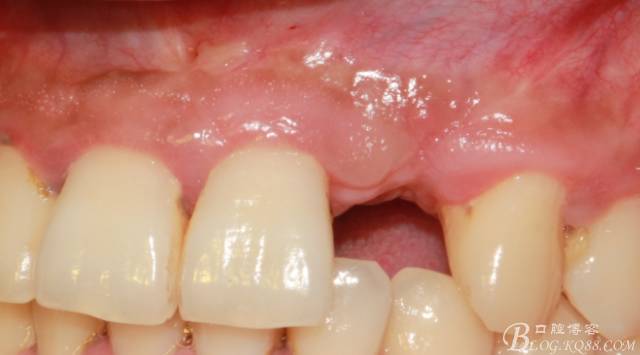

4個(gè)月后,唇側(cè)豐滿度尚可,與鄰牙之間齦乳頭完整。